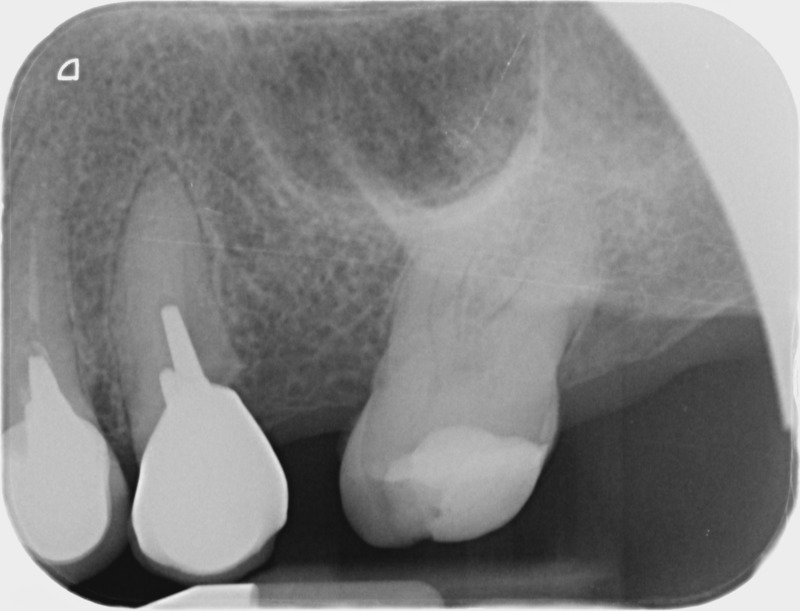

• Couronnes céramiques : Ce sont des prothèses dentaires esthétiques, avec parfois une armature métallique, destinées à rétablir l’anatomie fortement délabrée d’une couronne dentaire naturelle. Une fracture ou une lésion carieuse peut sérieusement endommager une dent qui aura alors besoin d’une couronne périphérique artificielle pour assurer sa conservation. Le soin dit de « dévitalisation » ne prévoit pas systématiquement la protection de la dent par une couronne, l’indication est à évaluer en fonction de la perte de tissu dentaire. De la même manière une dent vivante peut nécessiter la pose d’une couronne céramique sans que nous envisagions de retirer le nerf de ses racines. La couronne « tout céramique », en plus de permettre une reproduction fidèle et esthétique de l’anatomie dentaire, assure un grand confort au patient par sa biocompatibilité.

Avant